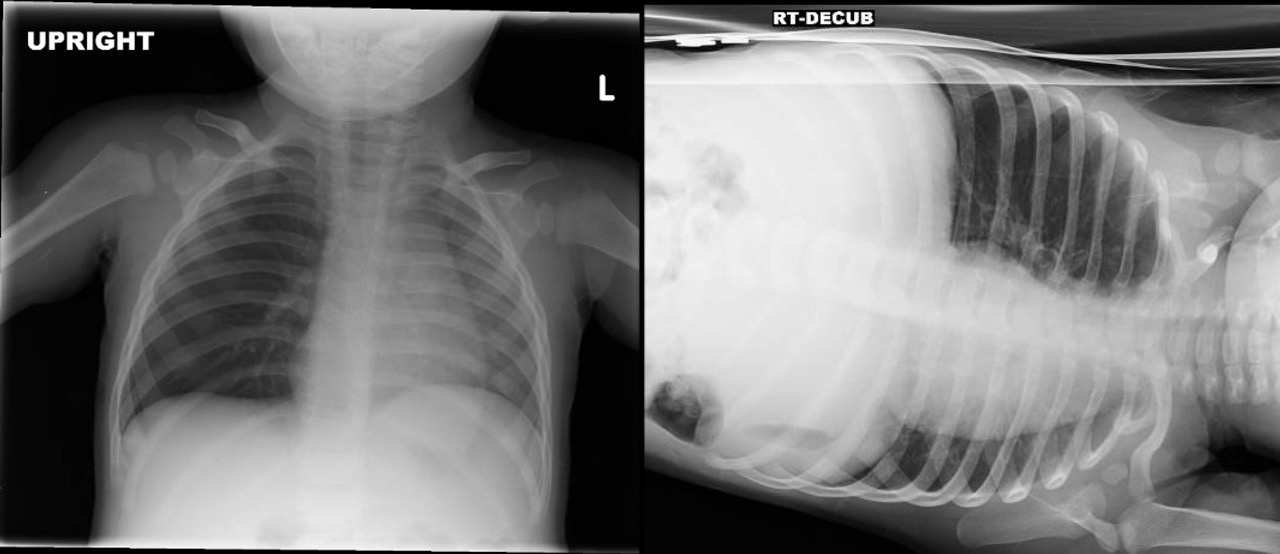

There typically is a delay in presentation for children who aspirate foreign bodies, which can make the diagnosis even more elusive. Approximately 50% to 70% of patients present within the first 24 hours of the aspiration event. The provider must have a high degree of clinical suspicion and ask caregivers about any recent choking events. On physical exam, providers should assess for decreased breath sounds on one side, usually right-sided given the angle of the bronchus, and lack of improvement with asthma treatment. It also is important to consider that, although only 20% of foreign bodies are radiopaque, abnormal findings are present in 40% to 80% of cases. If there is a suspicion for foreign body, perform a two-view X-ray. (See Figure 2.) Either inspiratory/expiratory films or decubitus vies which will demonstrate air trapping on the affected side.

Figure 2. Chest X-Ray with Bronchial Foreign Body |

Images courtesy of Aaron Leetch. Pediatric Emergency Medicine Reports, January 2016. |